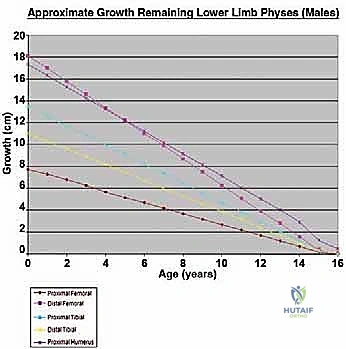

The core, absolute indication for an expandable prosthesis is the anticipated limb-length discrepancy at skeletal maturity. For the lower extremity, if the estimated leg-length discrepancy is calculated to be more than 3 cm, an expandable prosthesis is unequivocally indicated. Discrepancies exceeding 3 cm lead to severe pelvic obliquity, compensatory scoliosis, and significantly increased energy expenditure during ambulation. For projected discrepancies less than 3 cm, we might consider conventional "adult-type" prostheses, manufactured slightly longer (up to 1.5 cm) to over-lengthen the limb acutely, or we may opt for a contralateral epiphyseodesis to equalize limb lengths at maturity.

Age, Chemotherapy, and Physeal Sacrifice

Bone tumors in children frequently occur in the metaphyseal region, directly adjacent to the most active growth plates (e.g., distal femur, proximal tibia). Achieving wide oncologic margins often necessitates the complete sacrifice of a major physis, leading to an immediate and profound growth arrest in that segment. Expandable prostheses are specifically designed to counteract this exact iatrogenic deficit. Furthermore, we must account for the systemic effects of neoadjuvant and adjuvant chemotherapy. Intensive cytotoxic regimens independently suppress global bone growth and delay skeletal maturation, further complicating LLD calculations and contributing to potential discrepancies.

Patient age and skeletal maturity are the final arbiters. Generally, females older than 11 years or males older than 13 years rarely require expandable prostheses. At these ages, the remaining growth potential of the affected physes usually translates to an estimated growth discrepancy of less than 3 cm. Utilizing an expandable implant in a patient nearing skeletal maturity exposes them to the mechanical risks of a complex device without the requisite benefit.

Beyond standard oncologic staging, we require specialized orthopaedic measurements. Measured full-length scanograms of both the affected and contralateral limbs are critical for calculating current limb length and templating the prosthesis. A standardized hand/wrist radiograph is obtained to estimate skeletal bone age using the Greulich and Pyle atlas. This provides a vastly more accurate prediction of remaining growth than chronological age alone. The Estimated Limb-Length Discrepancy (LLD) at skeletal maturity is then calculated. While traditionally derived using the Anderson and Green charts, the validated Multiplier Method has emerged as a highly accurate and simpler predictor, utilizing chronological age and a single length measurement to definitively determine if an expandable prosthesis is indicated.